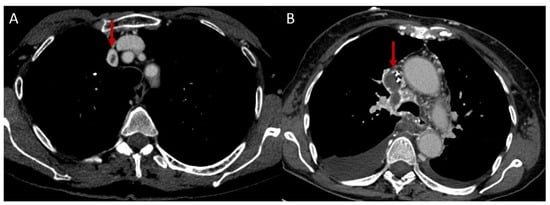

2.1.3. Systemic Veins

- Sheth, S.; Ebert, M.D.; Fishman, E.K. Superior Vena Cava Obstruction Evaluation with MDCT. AJR Am. J. Roentgenol. 2010, 194, W336–W346. [Google Scholar] [CrossRef]

- Qanadli, S.D.; el Hajjam, M.; Bruckert, F.; Judet, O.; Barré, O.; Chagnon, S.; Lacombe, P. Helical CT Phlebography of the Superior Vena Cava: Diagnosis and Evaluation of Venous Obstruction. AJR Am. J. Roentgenol. 1999, 172, 1327–1333. [Google Scholar] [CrossRef]

- Zhou, J.; Zhang, D.; Wang, Z.; Hou, Y.; Liu, J.; Zeng, X.; Wang, Y.; Zheng, W.; Zhou, J.; Zhang, D.; et al. The Clinical Features, Image Findings and Risk Factors of Vena Cava Syndrome in Behçet’s Syndrome Behçet’s Syndrome with Vena Cava Syndrome. Clin. Exp. Rheumatol. 2022, 40, 1526–1534. [Google Scholar]

- Sayeed, F.Z.; Nashit, M.; Bhatty, S.; Sayeed, B.Z.; Asad, F. A Case Report of Behcet’s Disease with Thromboses in the Superior Vena Cava and External Iliac Vein. Cureus 2022, 14, e24064. [Google Scholar] [CrossRef]

- Elzanaty, A.M.; Awad, M.T.; Acharaya, A.; Sabbagh, E.; Elsheikh, E.; Abdalamir, M. Superior Vena Cava Thrombosis and Dilated Cardiomyopathy as Initial Presentations of Behcet’s Disease. Thromb. J. 2020, 18, 1–4. [Google Scholar] [CrossRef]

- de Paiva, T.F.; Ribeiro, H.B.; Campanholo, C.B.; Gonçalves, C.R.; Terigoe, D.Y.; Souza, B.D.B. Behçet’s Disease Associated with Superior Vena Cava Syndrome without Thrombosis. Clin. Rheumatol. 2007, 26, 804–806. [Google Scholar] [CrossRef] [PubMed]

- Harman, M.; Sayarlioglu, M.; Arslan, H.; Ayakta, H.; Harman, E. Fibrosing Mediastinitis and Thrombosis of Superior Vena Cava Associated with Behçet’s Disease. Eur. J. Radiol. 2003, 48, 209–212. [Google Scholar] [CrossRef]

- Nair, A.A.; Christopher, D.J.; Moidu, F.; Chandran, D. Superior Vena Caval Obstruction: A Rare Presentation of Behcet’s Disease. BMJ Case Rep. 2020, 13, e236658. [Google Scholar] [CrossRef]

- Uyaroglu, O.A.; Erden, A.; Kilic, L.; Peynircioğlu, B.; Karadag, O.; Kalyoncu, U. Behçet’s Disease; A Rare Refractory Patient with Vena Cava Superior Syndrome Treated with Infliximab: A Case Report and Review of the Literature. Acta Clin. Belg. 2019, 74, 364–369. [Google Scholar] [CrossRef]